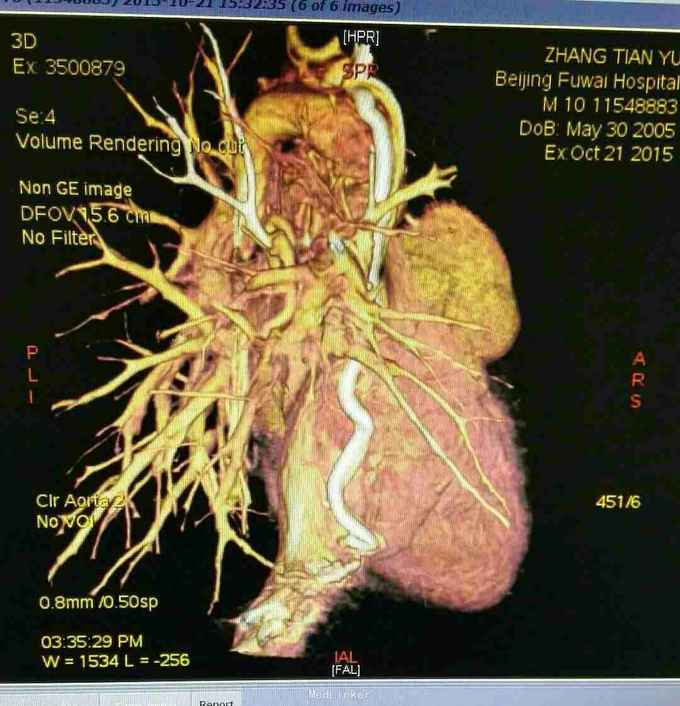

查体 生命体征平稳,口唇发绀,双肺呼吸音清,未闻及干湿性罗音,心律规整,于胸骨左缘可闻及杂音,腹部平软无压痛反跳痛,双下肢无水肿。 辅助检查 心脏彩超示 先天性心脏病 双向Glenn术后 单心室 大动脉转位 肺动脉瓣重度狭窄 上腔静脉-右肺动脉吻合口通畅。 心脏CT 先天性心脏病 双向Glenn术后 单心室 大动脉转位 肺动脉瓣重度狭窄 上腔静脉与右肺动脉连接。

诊断 先天性心脏病 双向Glenn术后 单心室 大动脉转位 肺动脉瓣重度狭窄。 治疗 患者入院后完善各项术前检查及准备,在全麻体外循环下行全腔静脉肺动脉吻合术,手术过程顺利,术后胸腔引流液增大,带胸骨8天引流液减少拔出引流管,患者顺利出院。 手术过程患者取仰卧位,常规消毒辅单,胸骨正中入路,小心分流心脏,建立体外循环,取人工血管将下腔静脉连接与肺动脉,同时结扎主肺动脉,辅助循环后减量停机,常规关胸安反监护室。